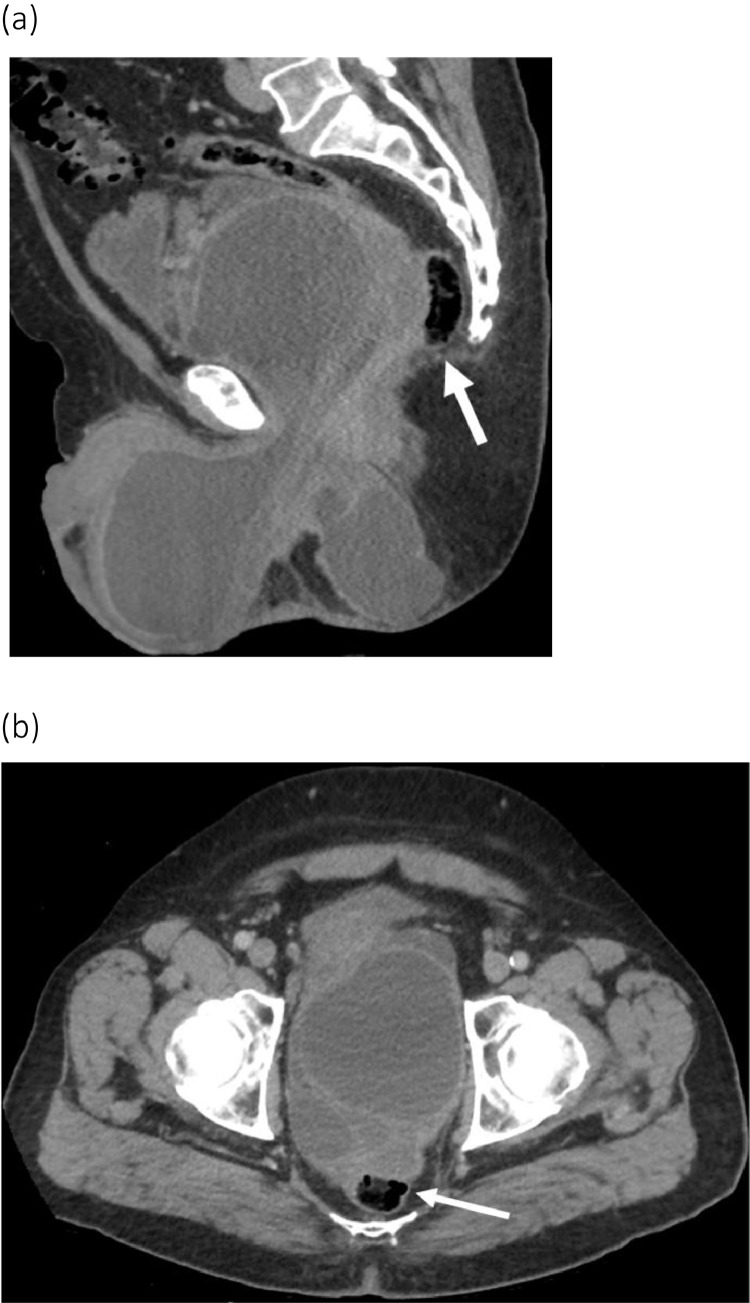

Fig. 2.

Recurrent extensive pelvic MCT in March 2017 despite four attempts at drainage and one abscess unroofing. Sagittal (a) and axial (b) contrast enhanced CT scan images contrast enhanced CT scan images showing a 25.4 × 13.5 cm multiloculated, rim-enhancing collection containing debris, extending through the pelvis and scrotum and perineum with mass effect on the rectum (arrow) and prostate.